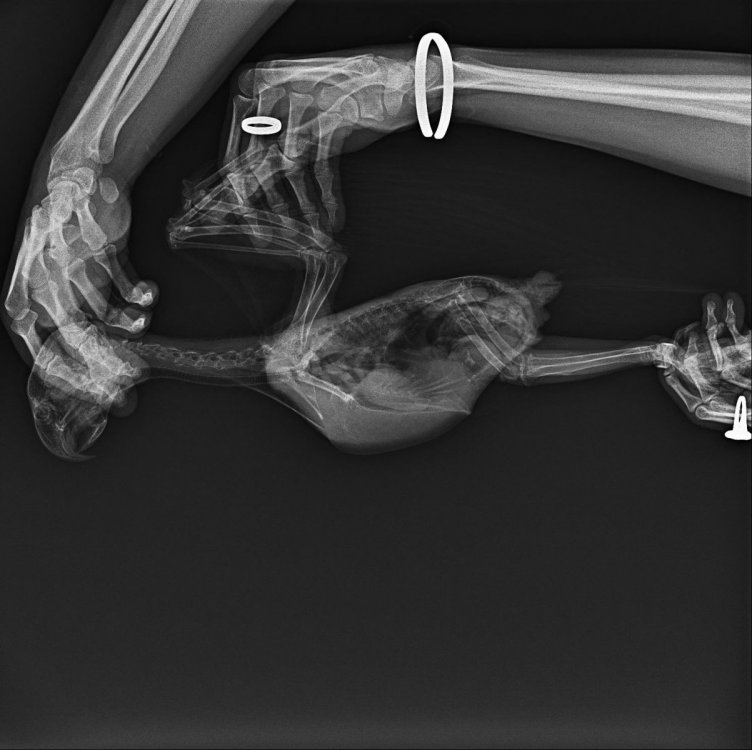

Arkasha18 Опубликовано 6 апреля, 2023 Автор #5 Опубликовано 6 апреля, 2023 в общем по итогу стул , то нормальный, то нет, прием доктора я тогда отменил, но тут он сильно заболеле и пришлось все таки отвезти, сделали рентген , взяли все анализы, не чего супер серьезного не нашли, но есть какие то на рентгене не пятна, сказали что это может быть ошибка ...нашли каието в помете грибы ...или что то там такое...в общем прописали всякого + антибиотик...и смотреть динамику надо сказали.

Arkasha18 Опубликовано 20 апреля, 2023 Автор #6 Опубликовано 20 апреля, 2023 Птица умерла ( только смог отойти от истории этой что бы что то написать. Куплена была птица у Андрея Михайлова возрастом 3 мес, на вторую неделю вот тут я писал что стул не нравится. но признаков болезни не была. птица была активная. Заводчик отговорил нести к доктору мотивировав что там его заколят, будет только хуже. через неделю птица простыла. я купил лампу ИК и черз два дня все прошло. Примерно через месяц после покупки попугая он опять заболел. пытались под лампой держать в отдельной комнате с теплыми полами. на третий день было понятно что что то серьезное. Он перестал кушать. сидел в низу клетки. понесли к доктору. были сделаны анализы. снимки. выписаны антибиотики. вечером мы его по поили антибиотиками. утром он был очень слаб уже. решили немного его покормить кашей 7 злаков без добавок со шприца. 5 кубов где то скормил. в 12 дня птица умерла. Вес был нормальный 500г. когда заболел скинул до 450 не уследил за какой период. Во всей этой истории очень грустно отношение ветеринаров. не хочу вдаваться в подробности но столько гадости в наш адрес было сказано что я в шоке. что нам птицу доверять нельзя и т/п/ я если честно в шоке. Заводчик отказался от компенсаций и отрекнулся тоже от происходящего. История ужасная еще тем что у меня жена беременная сильно все это переживала. я очень хочу купить еще одного птенца. теперь уже с анализами всеми и карантином как положено. но очень боюсь что повториться ситуация. это просто будет невыносимо. мы очень сильно горевали и до сих пор слезы наворачиваются. на видео последние минуты жизни ( вскрытие мы отказались делать потому что это и так было все сложно очень для нас. Посоветуйте как покупать новую птицу? где покупать. как обезопасить себя от таких ситуаций. рентген